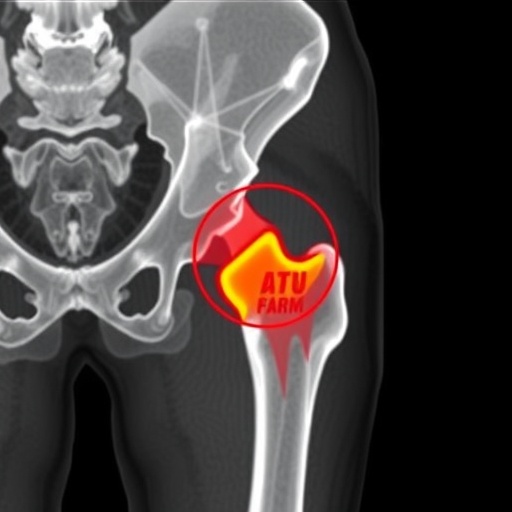

Intertrochanteric fractures, commonly occurring in older adults, particularly those with osteoporosis, pose surgical challenges that can result in complications, including fixation failure. The management of these fractures typically involves intramedullary nailing, a technique that has become standard practice due to its minimally invasive nature and favorable outcomes. However, the risk of failure remains a concern, and medical professionals continuously seek to enhance predictive methods that could improve surgical success rates. The use of CT scans provides a detailed analysis of bone density and structural integrity, vital factors that may influence the stability of the fixation.

In their investigation, the researchers utilized a cadre of CT measurements to quantify the attenuation of cortical bone in the proximal femur. This CT attenuation, measured in Hounsfield units (HU), serves as a surrogate marker for bone quality and density. Astonishingly, the findings reveal that lower CT attenuation values correlate significantly with higher rates of fixation failure. These compelling data suggest that assessment of bone quality through CT imaging preoperatively can provide key insights into patient eligibility for surgery and potentially improve surgical planning.